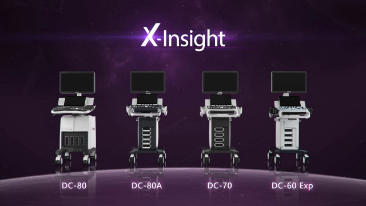

A solu??o totalmente nova da Mindray Ă© uma excelente transforma??o da vis?o permanente do cliente com base nas suas necessidades clĂnicas, combinada Ă s mais altas tecnologias de ultrassom em desenvolvimento.

O DC-70 com X-Insight, p?e o foco onde realmente importa e ajuda vocĂȘ a gerenciar as prĂĄticas clĂnicas diĂĄrias com facilidade e rigor.

Com base em uma profunda vis?o das necessidades do cliente, o DC-70 com X-Insight foi desenvolvido para oferecer diagnĂłsticos por imagens de alta eficiĂȘncia e com precis?o, o que Ă© possĂvel gra?as Ă Nitidez eXclusiva, InteligĂȘncia eXcepcional, eXceeding Experience.